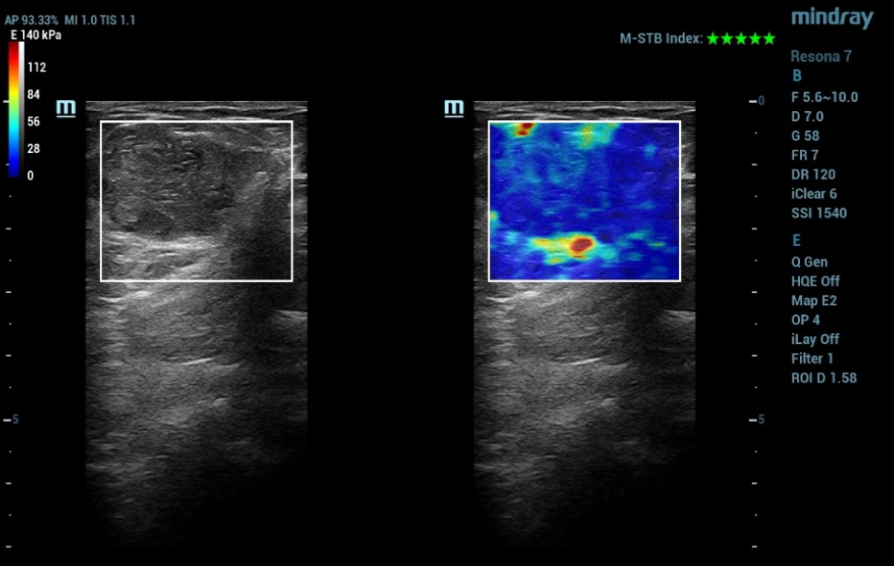

Ultrasound examination was performed on the Resona 7 ultrasound machine (Mindray, China) using a linear high-frequency transducer (up to 18 MHz). In the upper outer quadrant of the left breast, at 13 o'clock, an isoechoic horizontally oriented formation with a smooth, clear contour measuring 40x25 mm was determined (Fig. 1).

In the mode of elastography by a shear wave, the focal formation of the breast was uniformly colored in non-rigid blue tones (Fig. 4).

In this clinical example, the focal formation of the breast according to the BвАУmode and elastography by the shear wave was characterized as benign. According to the results of Doppler modes, there were signs of suspected neovascularization. Ultrasound with intravenous contrast also demonstrated increased vascularization of the formation with slow washout of the contrast agent. The quantitative analysis made it possible to objectify the data of qualitative analysis in the form of time-intensity curves and quantitative parameters.